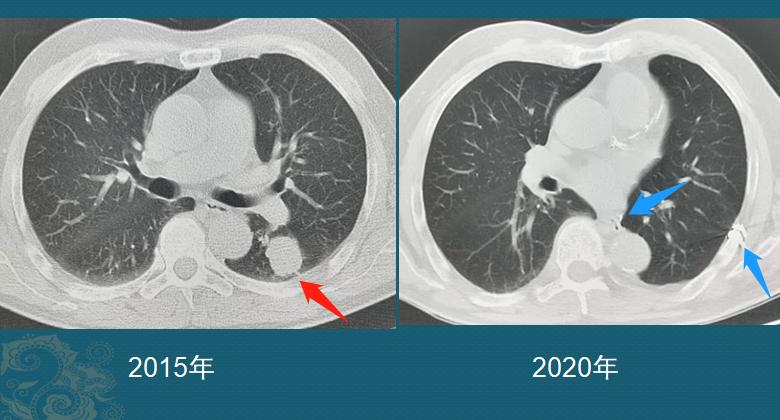

这是一个实性肺癌,长径>3cm,左肺下叶切除+淋巴结清扫+术后辅助治疗,5年多了没有复发,以后基本就不会复发了,每年定期体检一下就好,完全恢复正常生活。

老人拒绝了规范治疗,回家了。4个月后回来复查,1号和5号病灶增大了:

尤其是1号病灶,进入加速生长期了,4个月时间从3.5cm增大到4.6cm,提示癌细胞的繁殖速度非常快,非常凶狠。我们把1号病灶放大对比一下看:

箭头所示,是实性肺癌牵拉胸膜形成的胸膜凹陷征(从胸壁向肺内凹陷),呈喇叭口状,提示癌细胞侵犯胸膜,这是癌细胞的扩散途径之一,老人的颈部淋巴结转移,应该就是顺着这里扩散过去的。